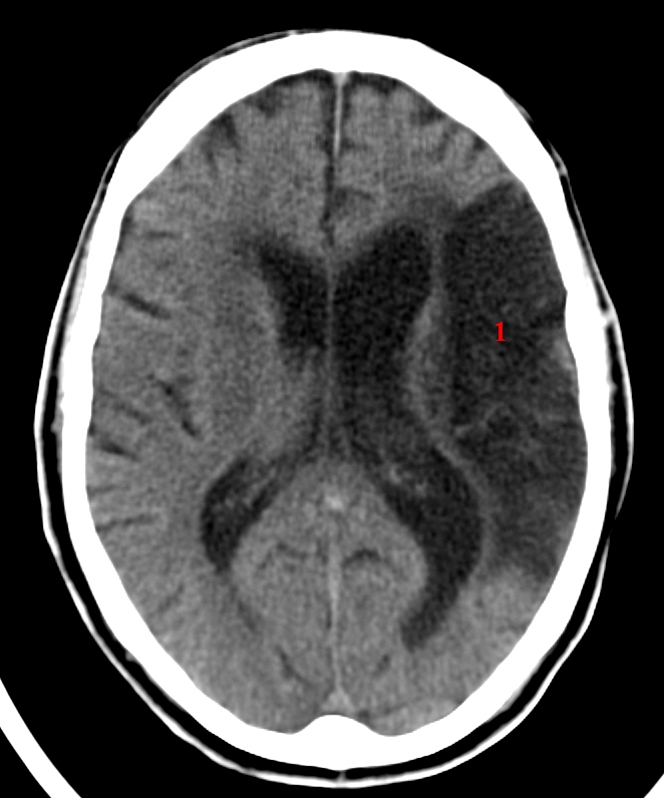

Wichtigstes diagnostisches Verfahren ist die kraniale CT um eine ursächliche Blutung auszuschließen. A cerebelli superior SCA. DT hjärna visar att mer än hälften av arteria cerebri medias kärlterritorium är infarktomvandlat och begynnande masseffekt.

Dens artery sign oder deutsch Dichte-Media-Zeichen linkes lecturiode 472 396 Leitsymptom Tumor 476 397 Epizootien Hautveränderungen durch tierische Parasiten 478 40 Neurologische Erkrankungen 480 402 Leitsymptom akute Halbseitenlähmung 481 booksgooglede. Der Mediainfarkt ist die häufigste Form des Schlaganfalls und führt zum Mediasyndrom dessen einzelne Symptome unterschiedlich stark ausgeprägt sein können und von der Ausdehnung und der Lokalisation des Infarktes abhängen. DT hjärna visar att mer än hälften av arteria cerebri medias kärlterritorium är infarktomvandlat och begynnande masseffekt. Frischer Infarkt im Stromgebiet der Arteria cerebri media mit sehr deutlichem dens media sign allgemeiner. Unvollständiger Mediainfarkt Mediateilinfarkt kompletter Mediainfarkt maligner Mediainfarkt. Bewusstseinsstörungen oder Koma häufig begleitet von Kopfschmerzen Übelkeit und Erbrechen sprechen für einen erhöhten Hirndruck der 4872 h nach einem ausgedehnten ischämischen Schlaganfall auftreten kann und sogar noch früher bei hämorrhagischen Insulten. Als Mediainfarkt bezeichnet man einen Hirninfarkt im Versorgungsgebiet der Arteria cerebri mediaMediainfarkte machen etwa 50 aller Hirninfarkte aus.